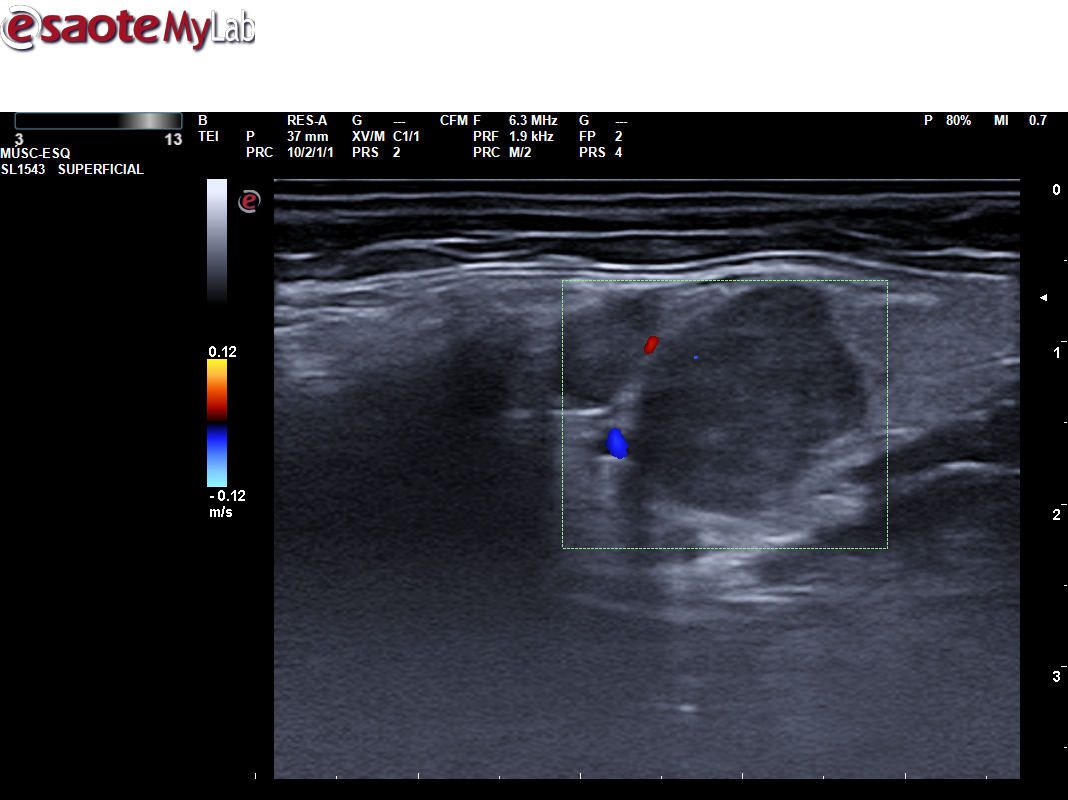

A través de distintos casos clínicos queremos valorar la importancia de la ecografía clínica en pacientes que consultan por la aparición de una masa cervical. Tras valorar a varios pacientes que han consultado por una masa cervical, hemos realizado una sesión clínica formativa sobre el aprendizaje de la ecografía cervical. Durante este periodo hemos podido diagnosticar diferentes patologías utilizando ecografía clínica y apoyándonos en otras pruebas complementarias, como un tumor de Merkel, un tumor de Warthin, una mononucleosis infecciosa, inflamación de un ganglio linfático por infección, un adenoma pleomorfo en glándula submandibular, malformación vascular, microlitiasis parotídeas, tuberculosis y un mieloma múltiple.

La ecografía ayuda a determinar las características de la masa, como su tamaño, forma y consistencia, lo que puede ayudarnos en la sospecha de patología maligna.

Permite distinguir entre diferentes tipos de tejidos, como quistes, ganglios linfáticos inflamados o tumores, lo que es crucial para un diagnóstico adecuado.

Si se necesita realizar una biopsia o drenaje, la ecografía puede guiar al médico para que lo haga de manera más precisa.